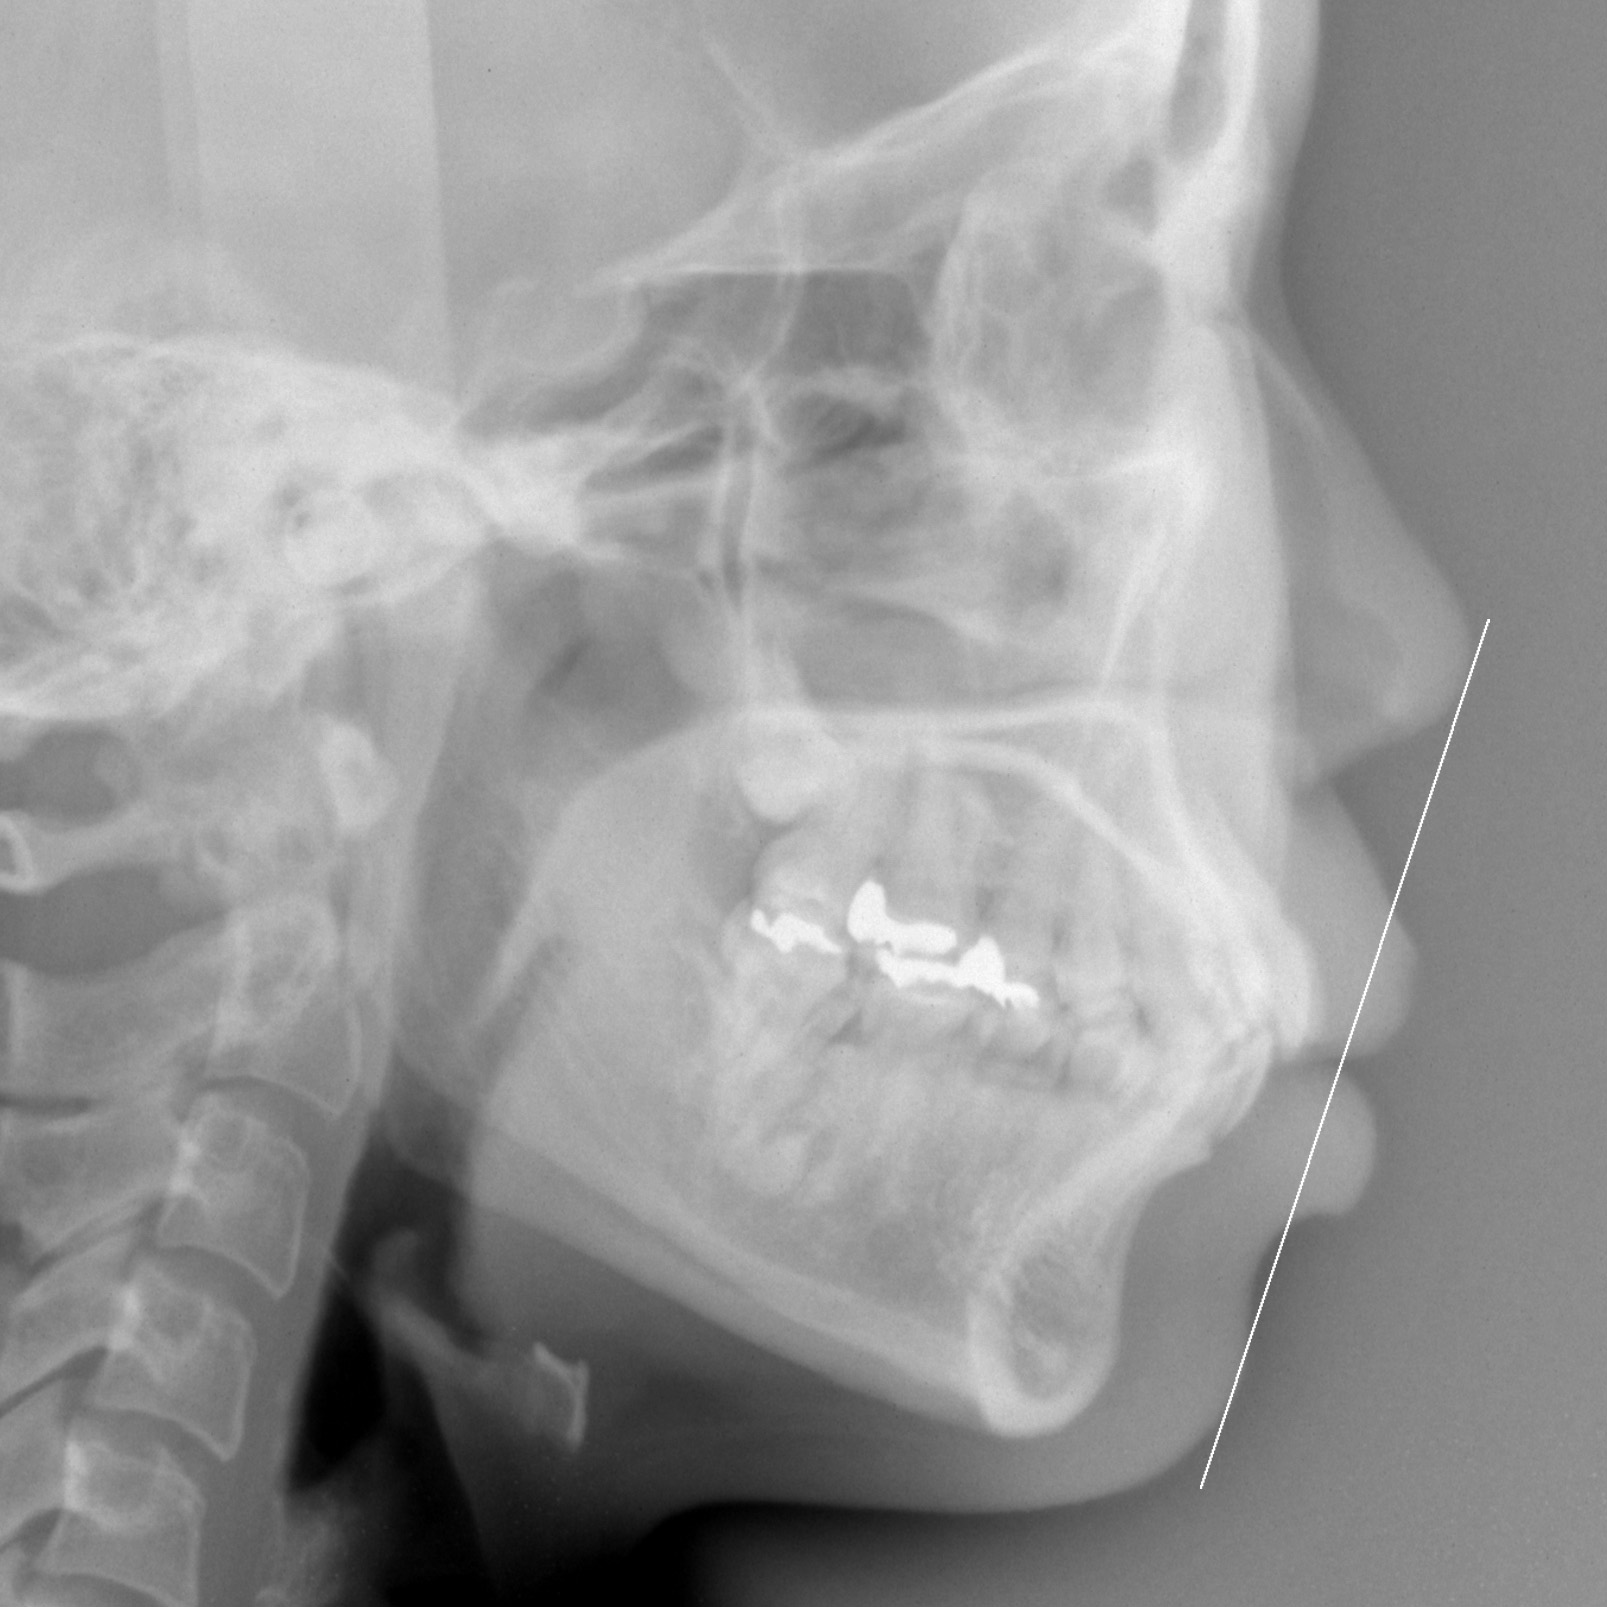

新着情報 939 治療前セファロ側面 – コピー Tweet 投稿日 : 2021年09月28日(火)カテゴリー : コメントを残す コメントをキャンセルメールアドレスが公開されることはありません。 * が付いている欄は必須項目ですコメント 名前 * メール * サイト 30歳 女性「 口もと を下げたい 」( 上下顎前突症 ) ≫